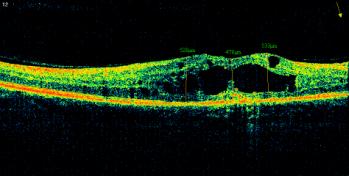

Рис. 2. ОКТ макулы и глазное дно

правого глаза пациента П. 52 лет, диагноз: ППДР, диффузный кистозный

макулярный отек.